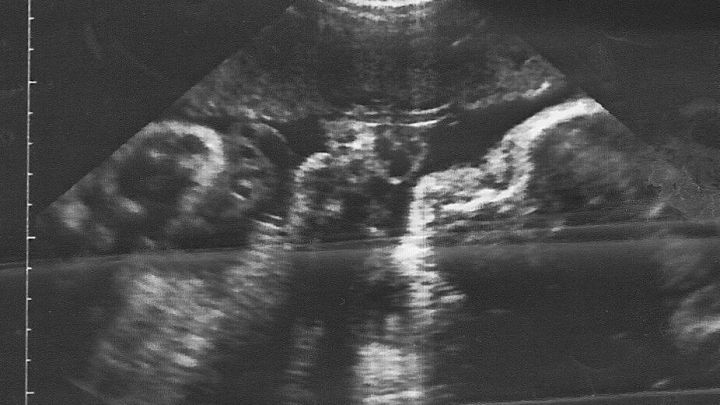

Ein Ultraschallbild zeigt das ungeborene Baby in einer Gebärmutter, umgeben von umgebenden Geweben und Flüssigkeit.